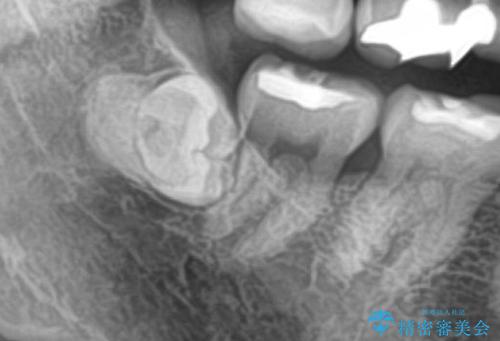

最新の症例

Latest cases